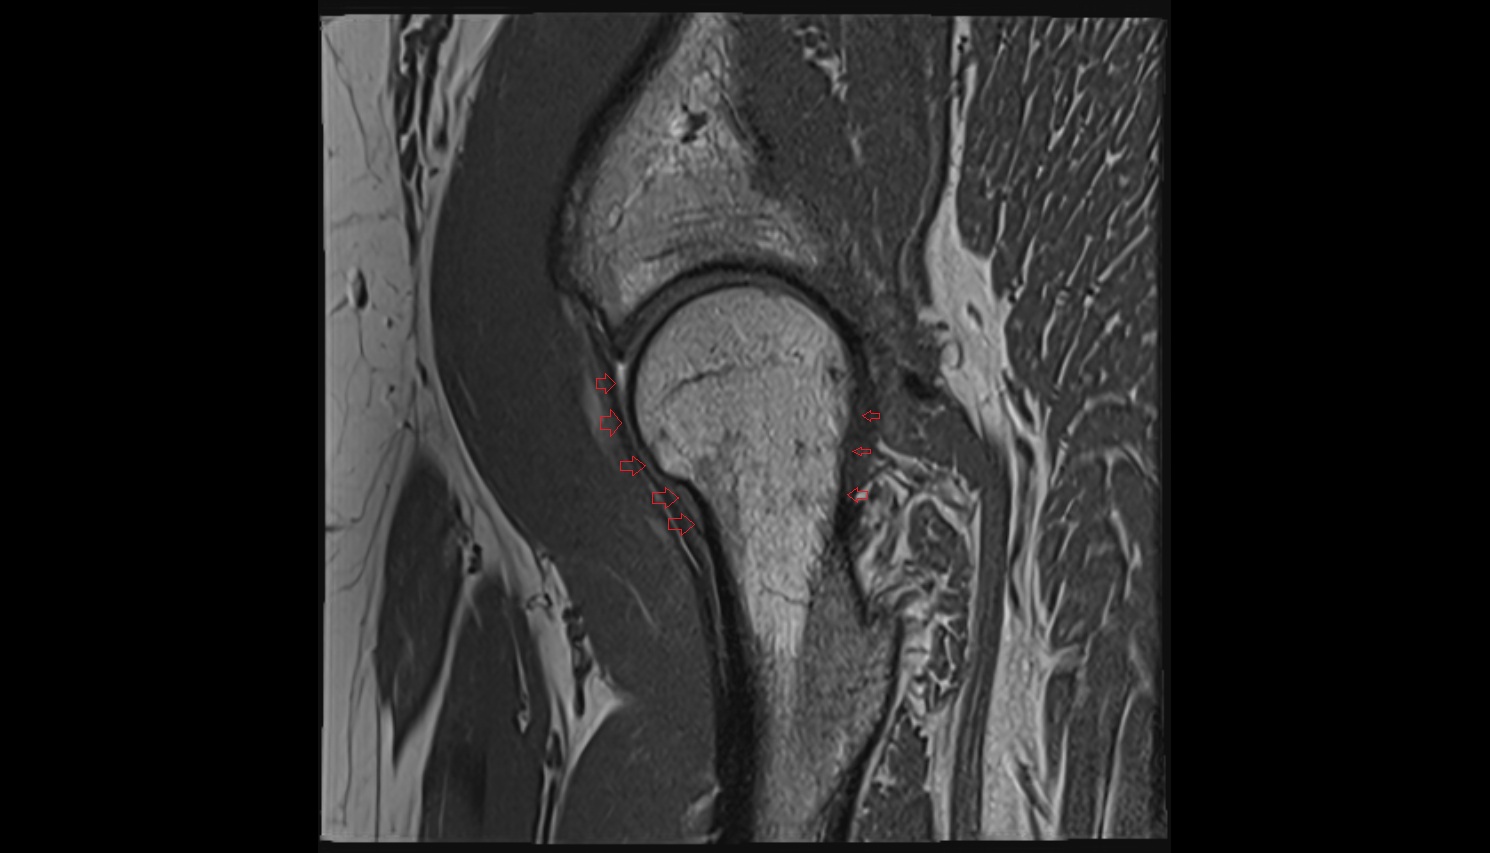

- Head of femur

- Neck of femur

- Hip joint